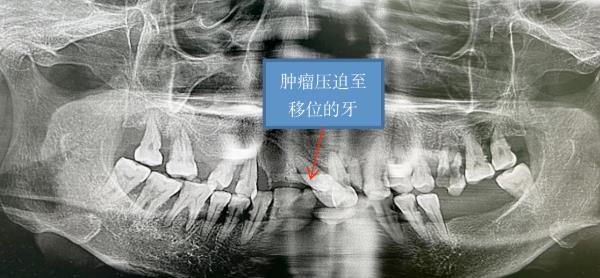

据悉,牙龈瘤是长在牙龈上的肿瘤,是来源于牙周膜及颌骨牙槽突结缔组织的炎性增生物或类肿瘤性病变,一般为良性肿瘤,由于来源于牙周膜,如不能切除牙周膜,手术后易复发,但很少恶变,女性多见,以青年及中年人最为常见,多长在牙龈乳头部,位于唇颊侧者较舌、腭侧者多。肿块较局限,为圆形或椭圆型,有时呈分叶状,大小不一。牙龈瘤长期位于口腔内,可影响口腔正常功能,牙龈瘤还可累及颌骨,可能造成口腔内骨组织缺损,牙龈瘤长期在口腔内可导致牙齿移位,影响口腔咬合功能。